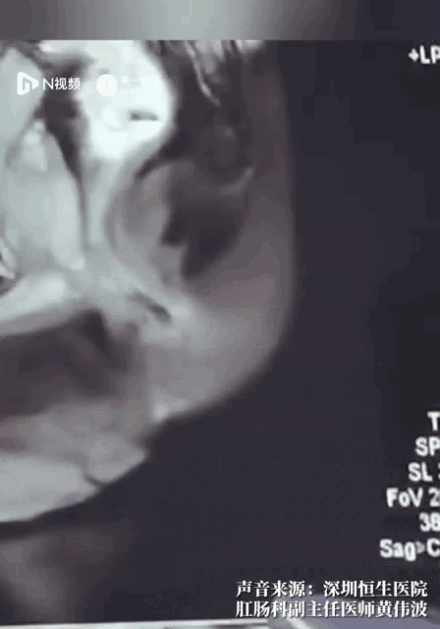

随后,医生对其进行影像检查,发现在其直肠与肛门处疑似有两个异物。

“在这个直肠的下段的异物,已经把肛门括约肌都刺破了。前期检查,为了给他止痛,我们给他打了两次止痛针,都不能缓解,患者曾经有一度痛得大汗淋漓,人都有点休克了。”

医生赶紧为谢先生安排手术。果然,在做手术时发现,有两根长达四公分长的鱼刺卡在直肠末端,鱼刺直接扎穿直肠,扎入了肛门括约肌当中。